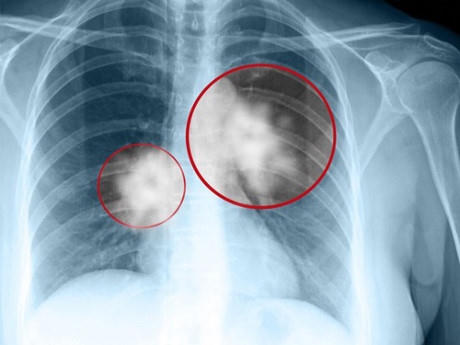

Được biết, trước khi qua đời nghệ sĩ Hán Văn Tình là bệnh nhân đã được điều trị lâu ngày tại Bệnh viện Ung bướu Hưng Việt. Nghệ sĩ Hán Văn Tình bị ung thư phổi có đột biến gen và có chỉ định điều trị thuốc đích. Khi bệnh nhân đã ở giai đoạn 4, di căn màng phổi và sau đó tiếp tục di căn não và xương thì được các bác sĩ tiếp tục chỉ định điều trị kết hợp hóa chất và xạ trị.

Theo các bác sĩ, hiện nay điều trị ung thư phổi tại các bệnh viện áp dụng theo phác đồ tiêu chuẩn trên toàn thế giới. Cụ thể, bệnh nhân giai đoạn một và hai phải phẫu thuật cắt bỏ khối u. Giai đoạn 3 cần xạ trị. Giai đoạn 4 sẽ dùng thuốc để kiểm soát. Tuy nhiên một số người bệnh ở giai đoạn một hoặc hai đã điều trị bằng phẫu thuật mà vẫn bị tái phát, bác sĩ thường chỉ định bổ sung thêm hóa chất để giảm nguy cơ.

Đối với bệnh nhân giai đoạn 3 có khối u ở phổi và xuất hiện hạch, phương pháp điều trị chính là xạ trị nhưng hiệu quả chỉ đạt khoảng 5 đến 8%. Vì thế, các bác sĩ thường chỉ định truyền thêm hóa chất để tăng thêm hiệu quả lên khoảng 20%.

Bệnh nhân giai đoạn 4, khi ung thư di căn, việc điều trị chỉ dừng lại ở mục tiêu kiểm soát bệnh nhằm kéo dài thời gian sống càng lâu càng tốt. Hiện có nhiều loại thuốc điều trị trúng đích thế hệ mới đã được kiểm chứng giúp gia tăng thời lượng sống cho người bệnh.